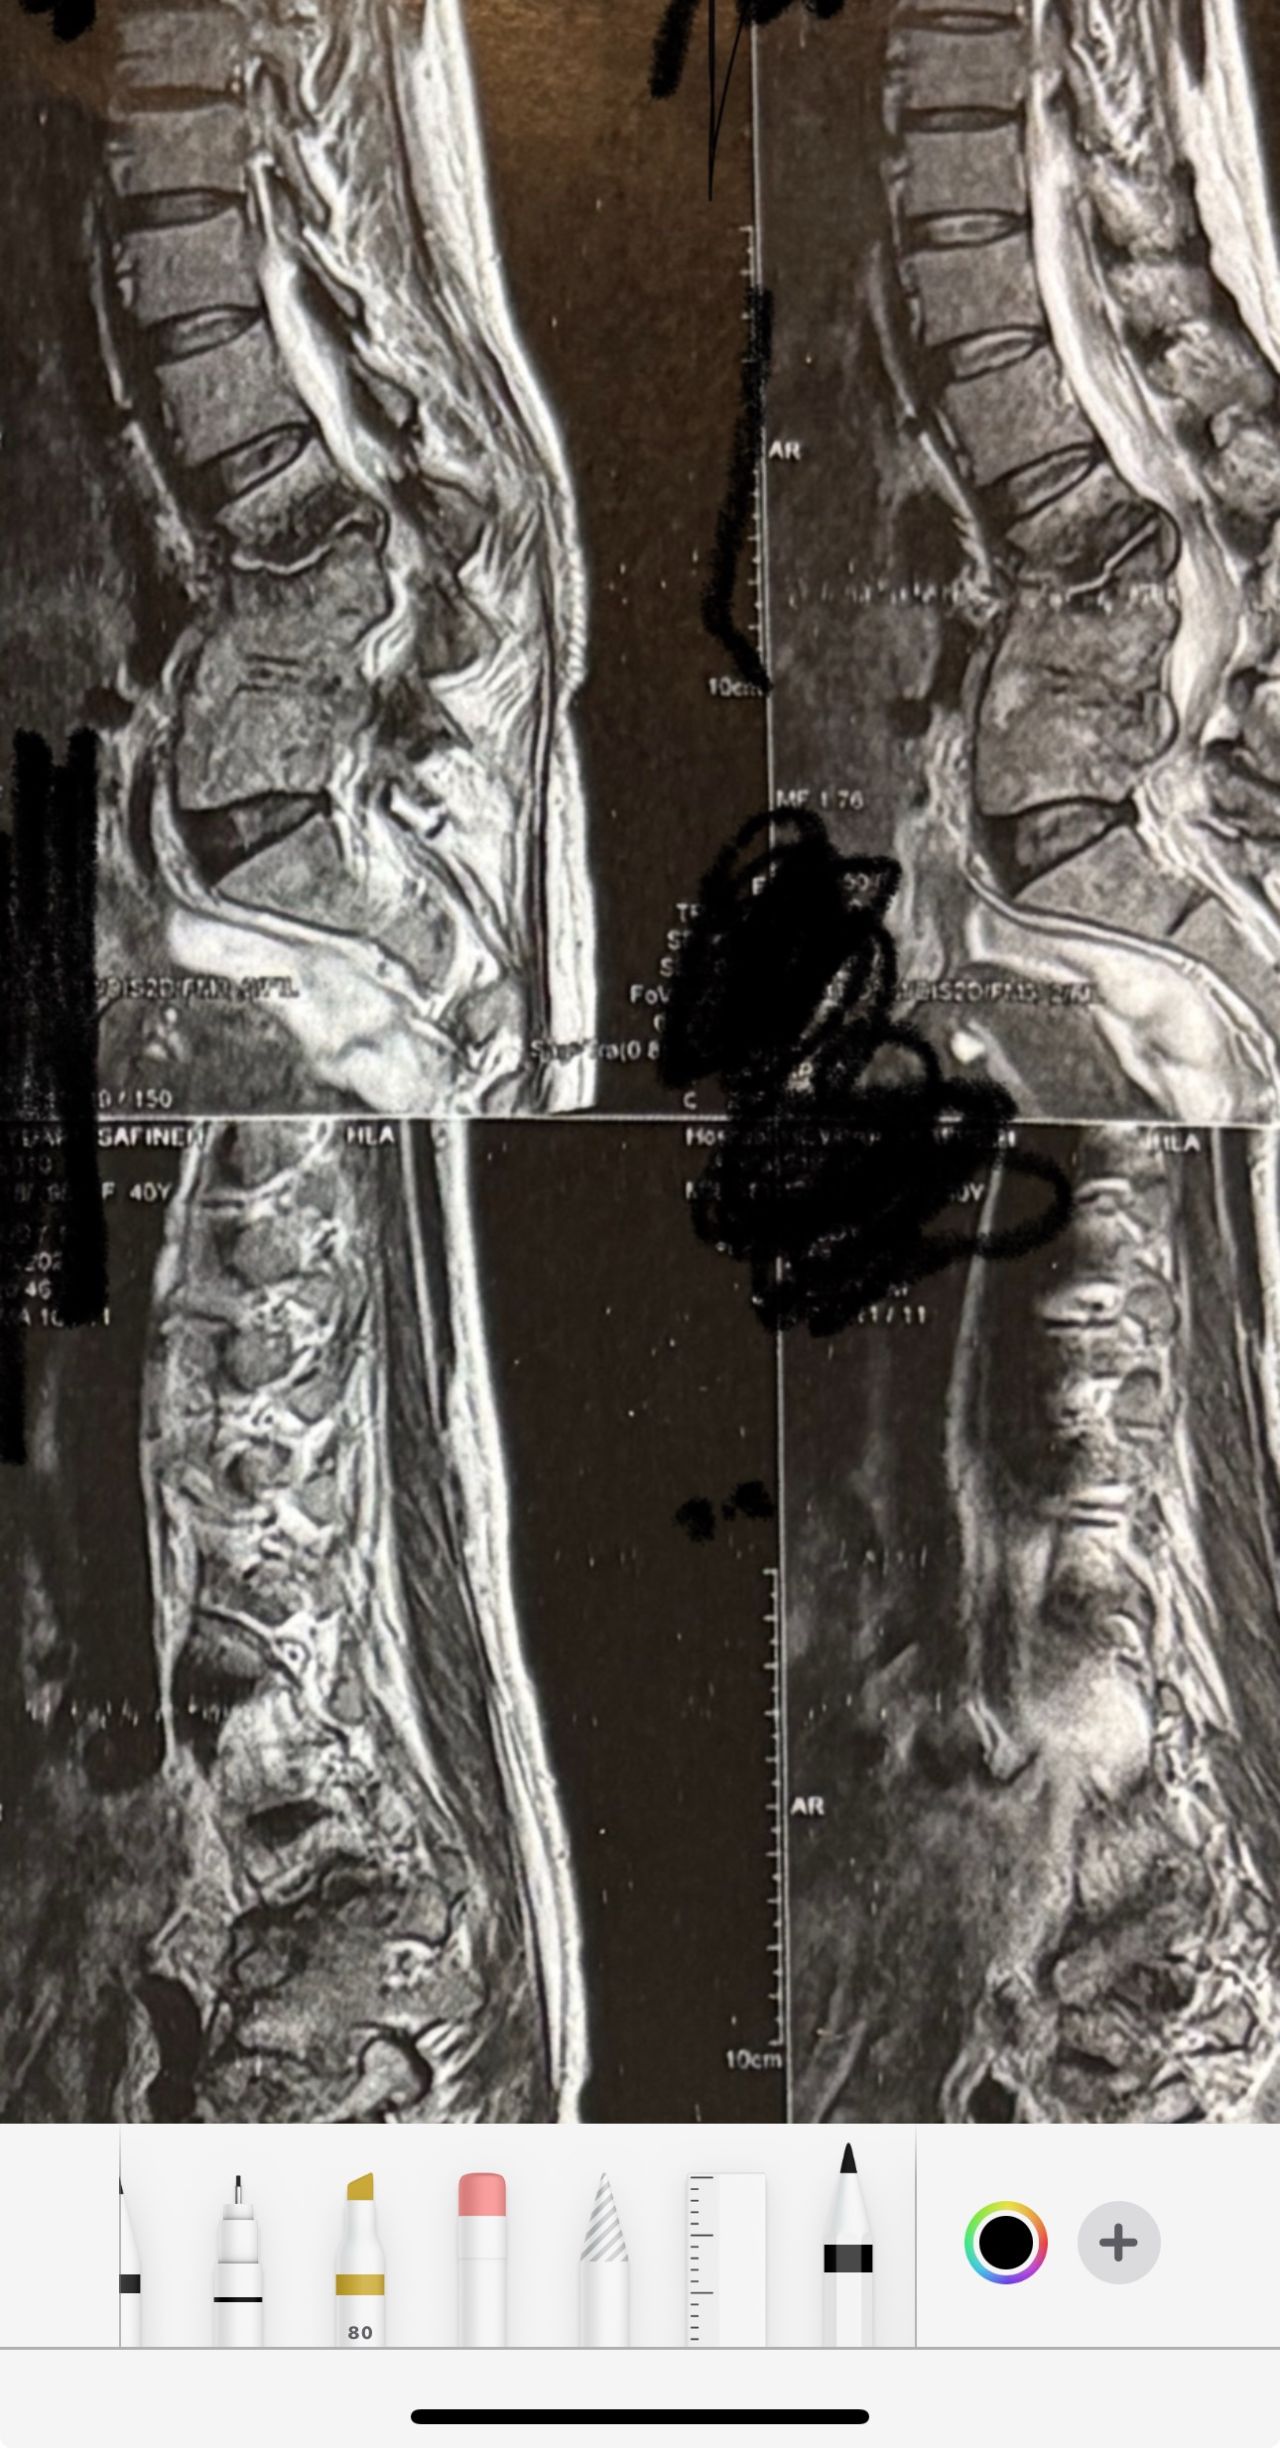

32 years female patient presented to my office one year ago with moderate cervical pain and R. Arm pain ,mild LBP with no radicular pain. Her mri in C/s had few bulges and few segmentsl dysfunctions

Her lumbar mri showed Contained R. Para. L5-S1 extrusion

She got treatment just for her neck and exercises for her low back. Few months later had lumbar disc surgery

Few days ago on may on june 08/2025, presented with severe LBP and no radicular pain

I have post her lumbar MRI before and after surgery. I consulted with a neurosurgeon at our clinic and he said doesn’t need another surgery because doesn’t have radicular pain or neurological deficits

For her pain i have started to do mild decompression by Cox and DTS and acupuncture, no adjustment whatsoever.

Please mention what differences you see before and after surgery